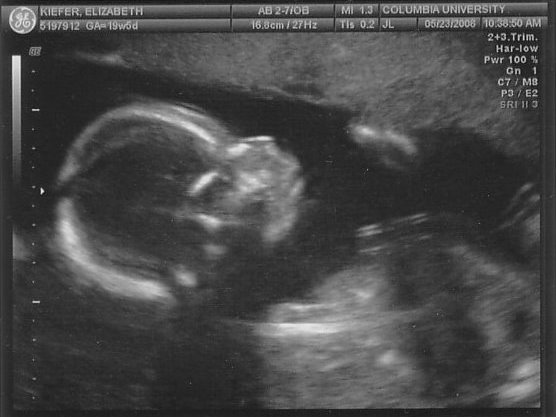

It’s a BOY!

… more photos of our baby, now verified as our little man. We had the ultrasound last Friday and he was squirming around, but we still have some nice pictures! He’s about the size of a banana now at 20 weeks, according to my pregnancy books. I’m not feeling any kicks yet, but hopefully soon!